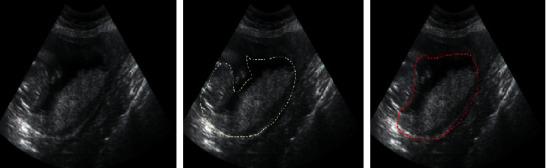

The study focused on the clinical diagnostic value of color Doppler ultrasound of dangerous placenta previa patients under the guidance of intelligent recognition algorithms. 58 patients with placenta previa and placenta accreta admitted to the hospital for treatment were selected as research subjects. The color Doppler ultrasound under the guidance of intelligent recognition algorithm was compared with the two-dimensional ultrasound for specificity, sensitivity, and accuracy. The color Doppler ultrasound results showed that, of the 58 patients, there were 32 cases of complete placenta previa and 26 cases of incomplete placenta previa, which were consistent with the surgical pathology results. It was found that patients with malignant placenta previa and placenta accreta had thickened placenta, disappeared posterior placental space, myometrium <2 mm, and increased incidence of cervical enlargement (  0.05). In conclusion, the recognition accuracy of color Doppler ultrasound under the guidance of the intelligent recognition algorithm is more than 90%, and it can effectively identify dangerous placenta previa, assisting doctors in diagnosis and treatment of dangerous placenta previa.

该研究侧重于智能识别算法指导下的凶险性前置胎盘患者的彩色多普勒超声的临床诊断价值。选取因凶险性前置胎盘入院治疗的 58 例患者作为研究对象。比较智能识别算法指导下的彩色多普勒超声与二维超声的特异性、敏感性和准确性。彩色多普勒超声结果显示,58 例患者中完全性前置胎盘 32 例,不完全性前置胎盘 26 例,与手术病理结果一致。发现恶性凶险性前置胎盘和胎盘植入患者胎盘增厚、胎盘后间隙消失、肌层厚度<2mm、宫颈扩张发生率增加(  0.05)。结论:智能识别算法指导下的彩色多普勒超声的识别准确率超过 90%,可有效识别凶险性前置胎盘,辅助医生对凶险性前置胎盘进行诊断和治疗。